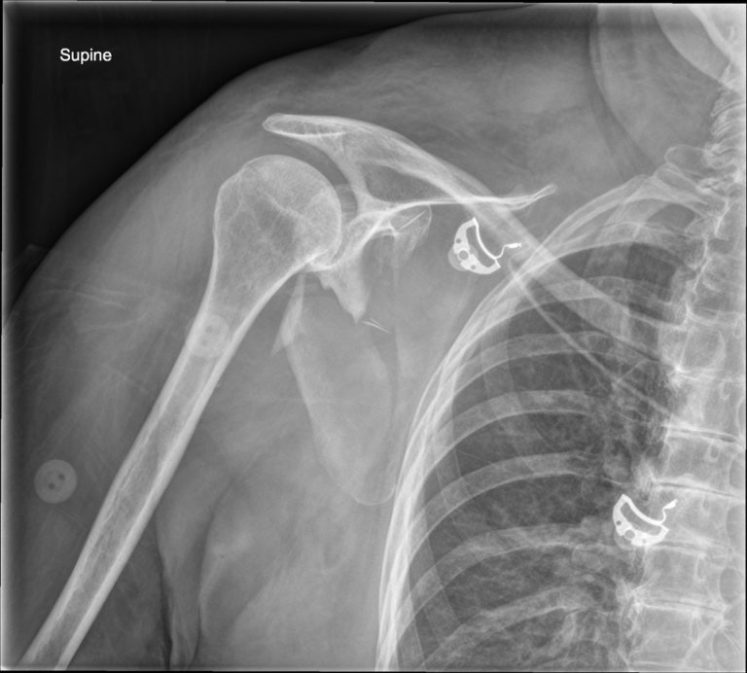

Scapula Fractures Gepost op 17 augustus 2018 door netwerkvsseh Scapula Fractures @coreem.net Dit delen: Delen op X (Opent in een nieuw venster) X Share op Facebook (Opent in een nieuw venster) Facebook Delen op LinkedIn (Opent in een nieuw venster) LinkedIn E-mail een link naar een vriend (Opent in een nieuw venster) E-mail Afdrukken (Opent in een nieuw venster) Print Vind-ik-leuk Aan het laden... Gerelateerd